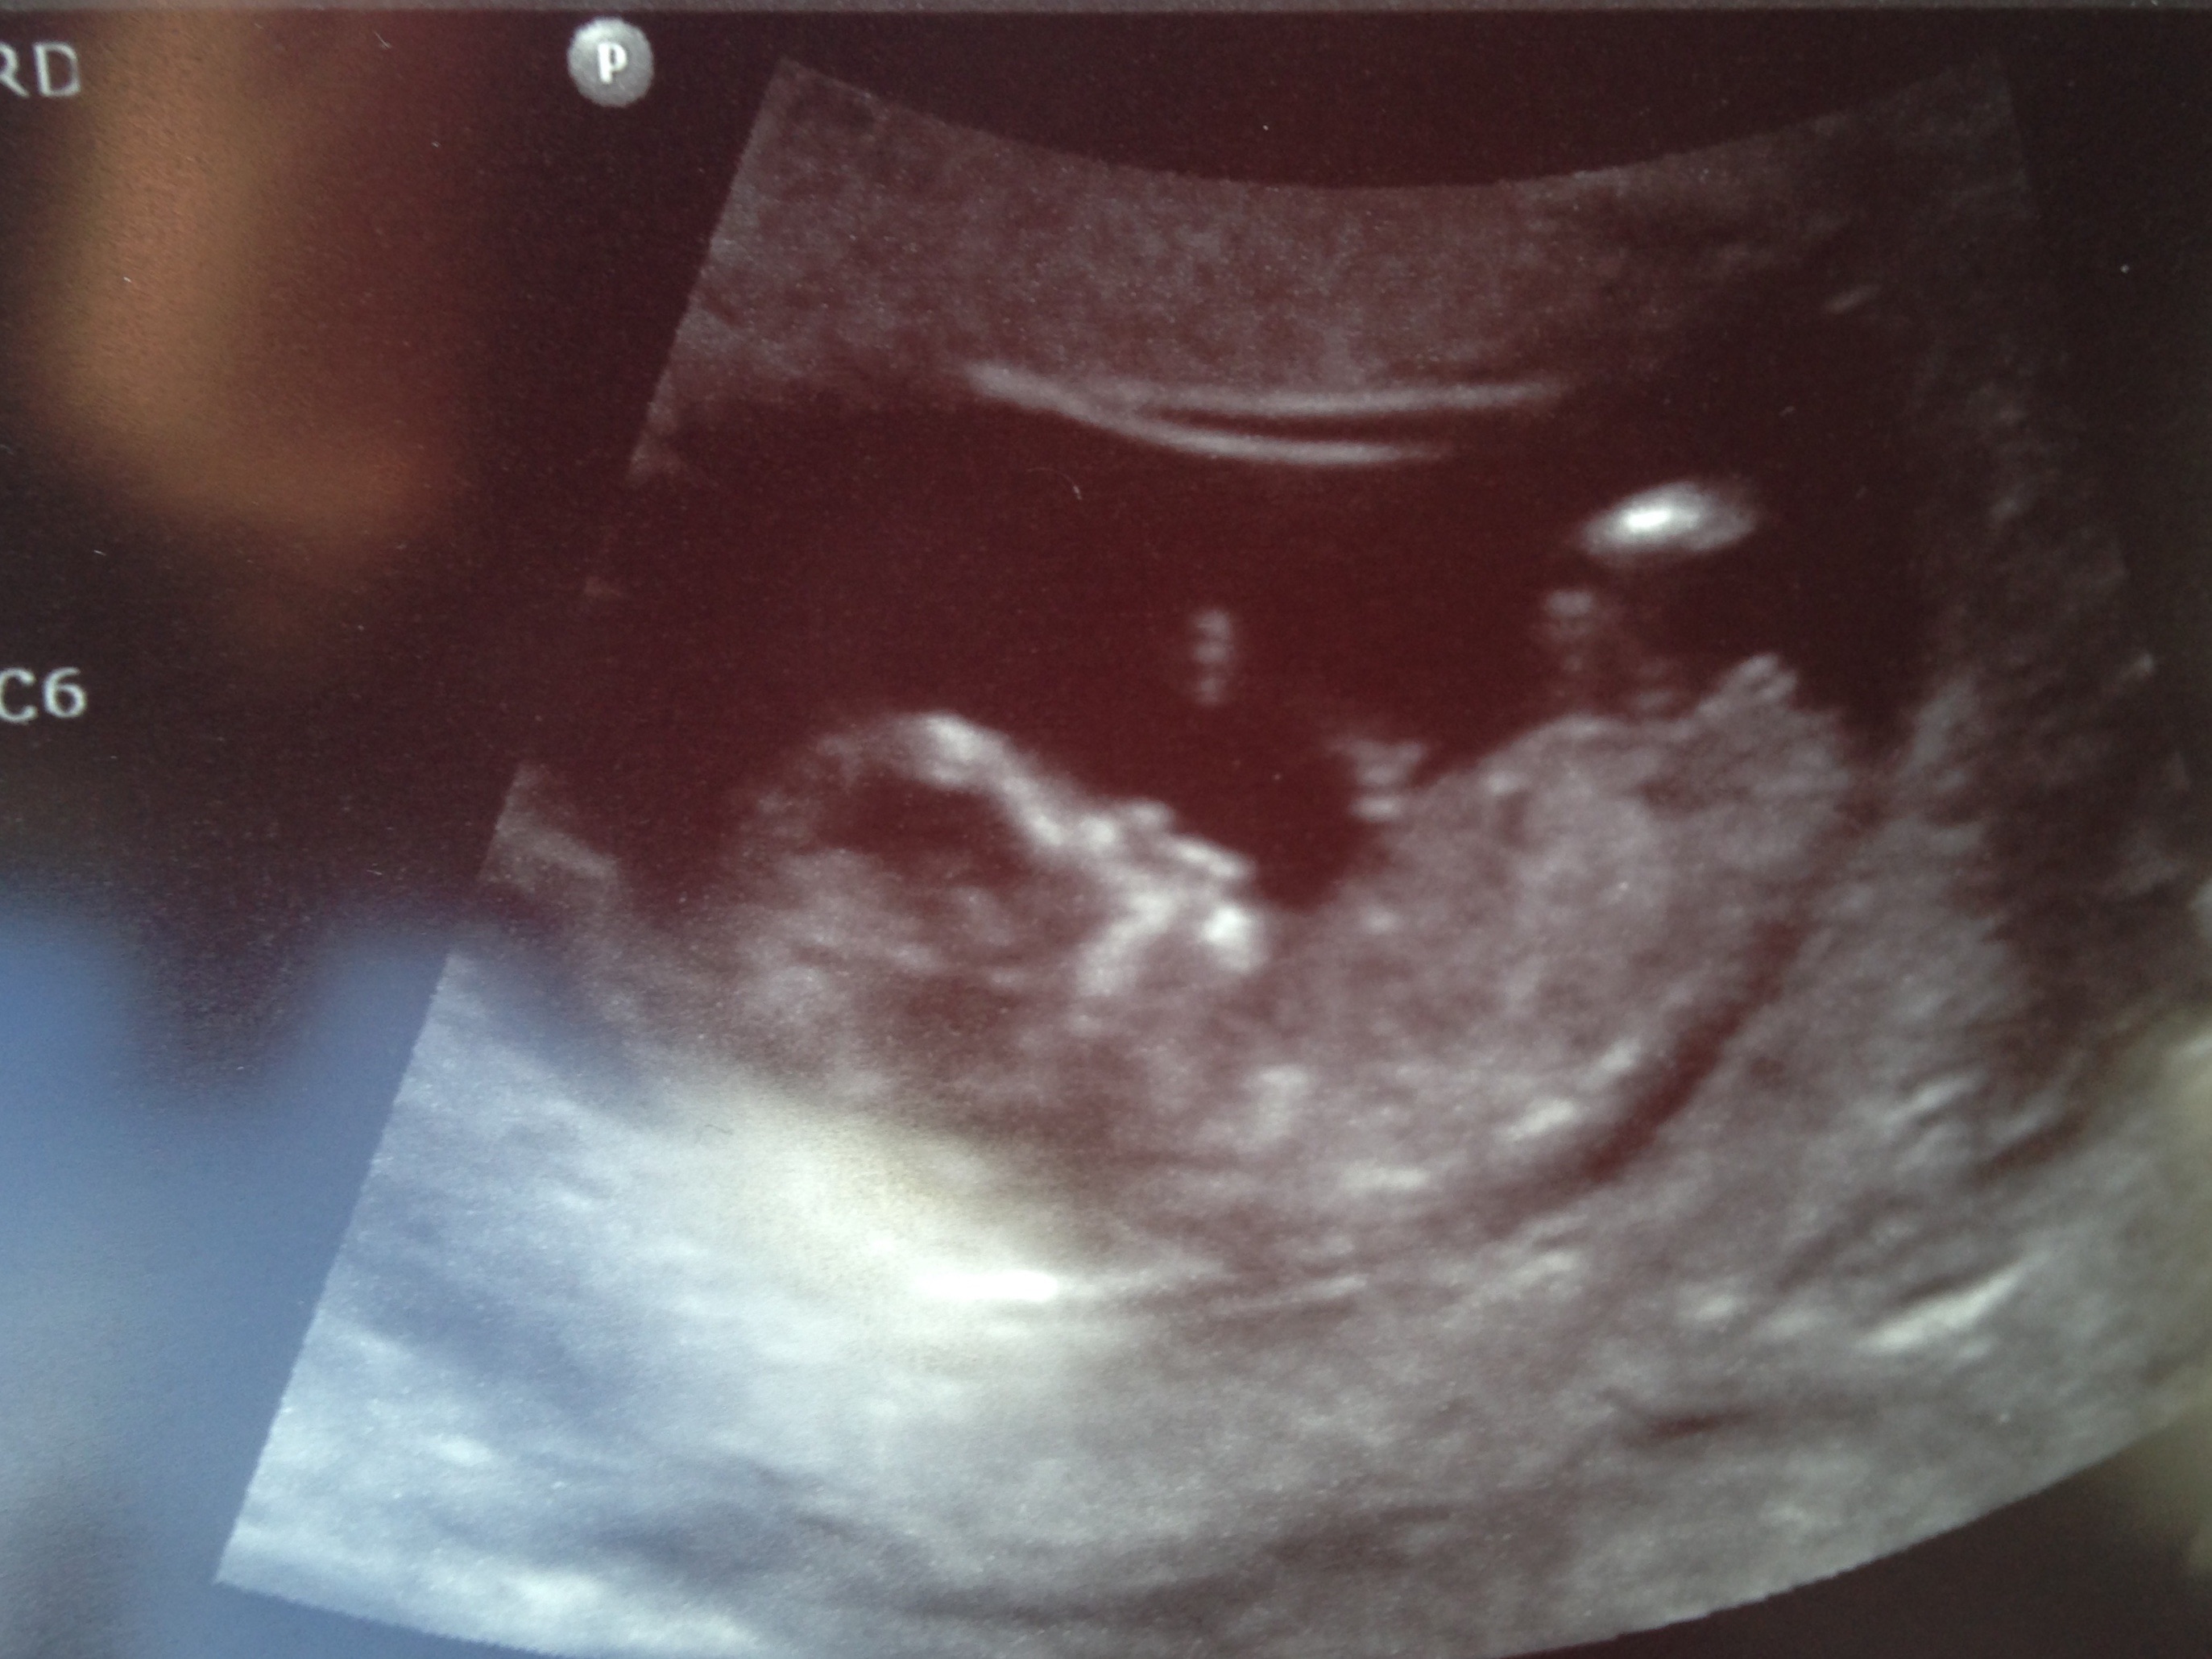

Not sure if you can tell from these but I'm curious.

12w6d

Then I'd say girl :)

You will get lots more guesses I'm not an expert on nubs but you have nice clear nubs there :)

girl

Girl!

Leaning girl too